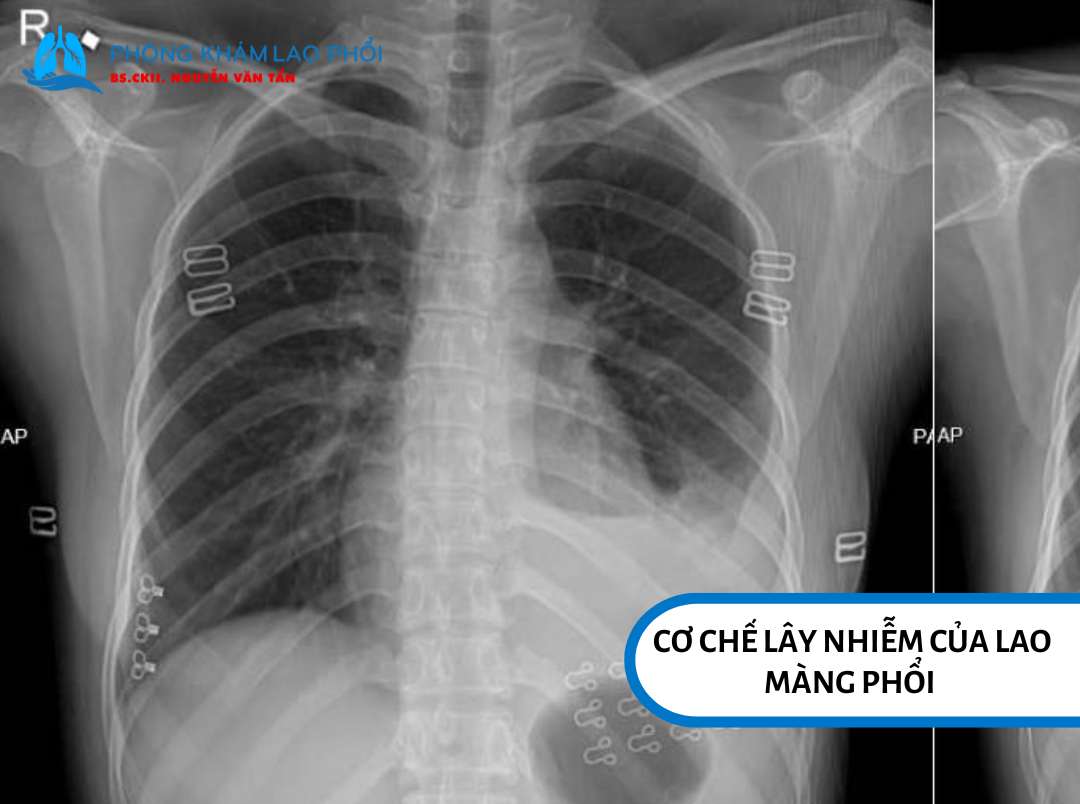

Cơ chế lây nhiễm của lao màng phổi theo từng giai đoạn

Cơ chế lây nhiễm của lao màng phổi thay đổi theo tiến triển của bệnh. Dưới đây là ba giai đoạn chính: